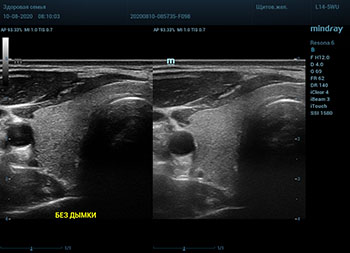

Ультразвуковое оборудование не отстает от современно тренда. В приборах серии Resona, компании Mindray, появилась новая функция постобработки изображения. Имя ей Dehaze. В переводе на наш родной язык – удаление дымки или рассеивание тумана. Инструмент позволяет корректировать интенсивность тумана или дымки. При этом сохраняется общий контраст и детализация картинки. Dehaze также позволяет проявлять детали снимка в гиперэхогенных зонах и снимать артефакты при чрезмерном усилении.

Готовый снимок или видео петля в формате DICOM несет в себе полное нативное изображение. Прибор позволяет, подобно легендарному фотошопу, удалить лишний «туман». Гиперэхогенный диффузный «засвет» изображения, из-за повышенного общего усиления, часто вредит обследованию. Однако без него некоторые вещи не видны. Показать гипоэхогенные участки и скрыть эхогенную дымку и позволяет Dehaze.

Всё что требуется от доктора – нажать кнопку или повернуть ручку. Мгновенная оптимизация. Мгновенно чистое изображение.